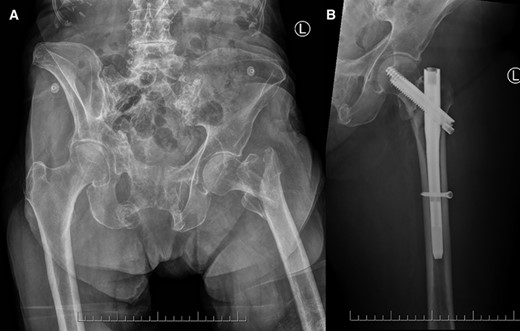

A 90-year-old woman suffered a mechanical fall at home, immediately developed left hip pain and inability to weight-bear, and was brought to the emergency room. Radiographs revealed a displaced intertrochanteric hip fracture with a separate greater trochanteric fragment (Fig. 1A). Her past medical history was significant for atrial fibrillation (on apixaban). At baseline, she lived at home as a 24-h caregiver and was independent in ambulation with a rollator walker.

Frontal radiographs demonstrating (A) the comminuted left intertrochanteric hip fracture with separate lesser and greater trochanteric fragments (left), and (B) the comminuted left intertrochanteric hip fracture treated with internal fixation with proximally and distally locked short cephalomedullary nails (right).

Two days after injury, she underwent internal fixation with proximally and distally locked short cephalomedullary nails. The procedure was uncomplicated and completion orthogonal fluoroscopic views confirmed appropriate fracture reduction with hardware in position and intramedullary throughout (Fig. 1B).